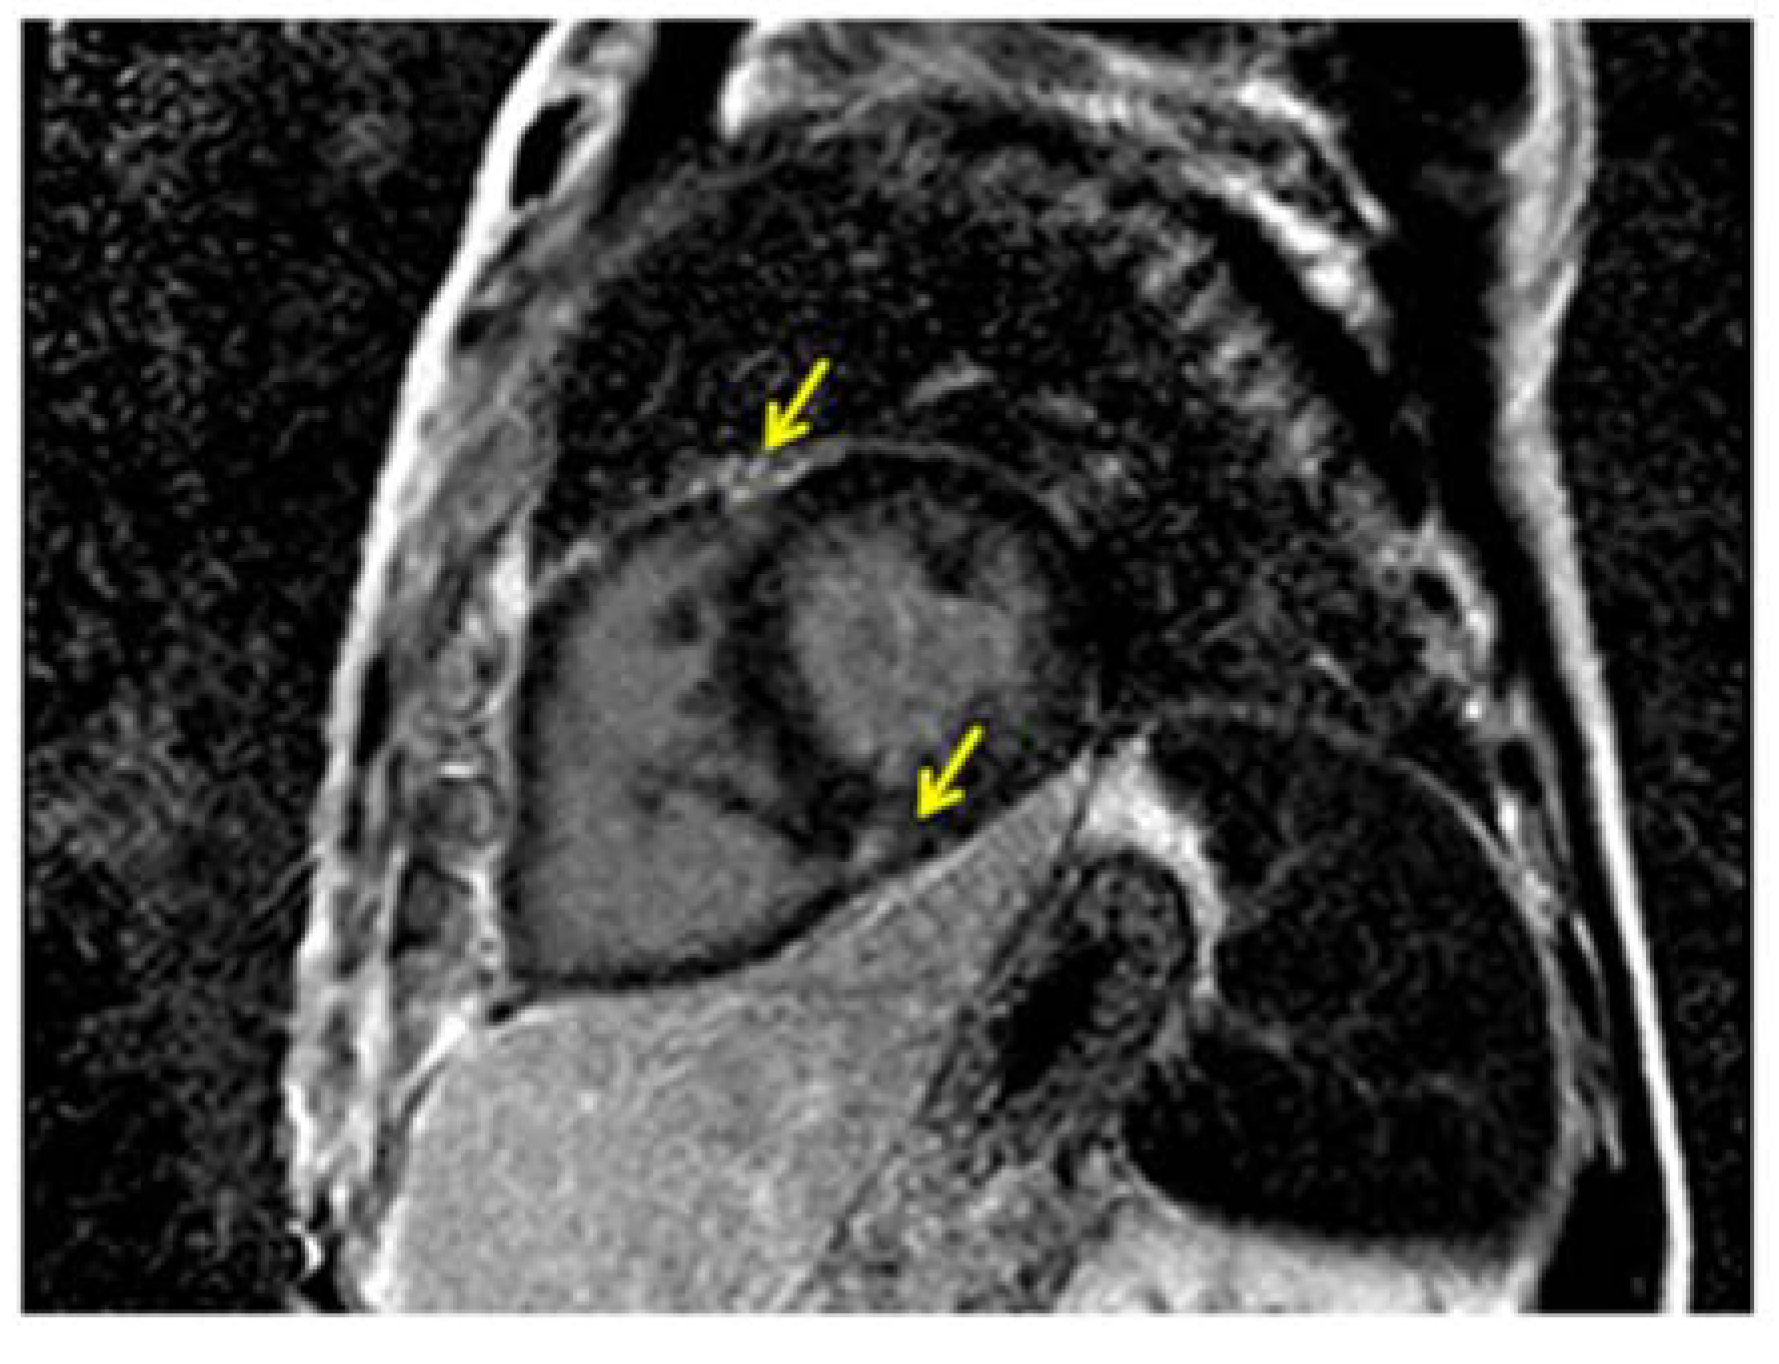

4. Cardiac Magnetic Resonance

- McCann, G.P.; Beek, A.M.; Vonk-Noordegraaf, A.; van Rossum, A.C. Delayed contrast-enhanced magnetic resonance imaging in pulmonary arterial hypertension. Circulation 2005, 112. [Google Scholar] [CrossRef]

- McCann, G.P.; Gan, C.T.; Beek, A.M.; Niessen, H.W.; Vonk Noordegraaf, A.; van Rossum, A.C. Extent of MRI delayed enhancement of myocardial mass is related to right ventricular dysfunction in pulmonary artery hypertension. Am. J. Roentgenol. 2007, 188, 349–355. [Google Scholar] [CrossRef]

- Blyth, K.G.; Groenning, B.A.; Martin, T.N.; Foster, J.E.; Mark, P.B.; Dargie, H.J.; Peacock, A.J. Contrast enhanced cardiovascular magnetic resonance imaging in patients with pulmonary hypertension. Eur. Heart J. 2005, 26, 1993–1999. [Google Scholar] [CrossRef] [PubMed]

- Sanz, J.; Dellegrottaglie, S.; Kariisa, M.; Sulica, R.; Poon, M.; O’Donnell, T.P.; Mehta, D.; Fuster, V.; Rajagopalan, S. Prevalence and correlates of septal delayed contrast enhancement in patients with pulmonary hypertension. Am. J. Cardiol. 2007, 100, 731–735. [Google Scholar] [CrossRef] [PubMed]

- Bradlow, W.M.; Assomull, R.; Kilner, P.J.; Gibbs, S.R.; Sheppard, M.N.; Mohiaddin, R.H. Understanding late gadolinium enhancement in pulmonary hypertension. Circ. Cardiovasc. Imaging 2010, 3, 501–503. [Google Scholar] [CrossRef] [PubMed]

- Sato, T.; Tsujino, I.; Ohira, H.; Oyama-Manabe, N.; Ito, Y.M.; Noguchi, T.; Yamada, A.; Ikeda, D.; Watanabe, T.; Nishimura, M. Paradoxical Interventricular Septal Motion as a Major Determinant of Late Gadolinium Enhancement in Ventricular Insertion Points in Pulmonary Hypertension. Plos One 2013, 8. [Google Scholar] [CrossRef]

- Freed, B.H.; Gomberg-Maitland, M.; Chandra, S.; Mor-Avi, V.; Rich, S.; Archer, S.L.; Jamison, E.B., Jr.; Lang, R.M.; Patel, A.R. Late gadolinium enhancement cardiovascular magnetic resonance predicts clinical worsening in patients with pulmonary hypertension. J. Cardiovasc. Magn. Res. 2012, 14. [Google Scholar] [CrossRef]

- Shehata, M.L.; Lossnitzer, D.; Skrok, J.; Boyce, D.; Lechtzin, N.; Mathai, S.C.; Girgis, R.E.; Osman, N.; Lima, J.A.; Bluemke, D.A.; et al. Myocardial delayed enhancement in pulmonary hypertension: pulmonary hemodynamics, right ventricular function, and remodeling. Am. J. Roentgenol. 2011, 196, 87–94. [Google Scholar] [CrossRef]